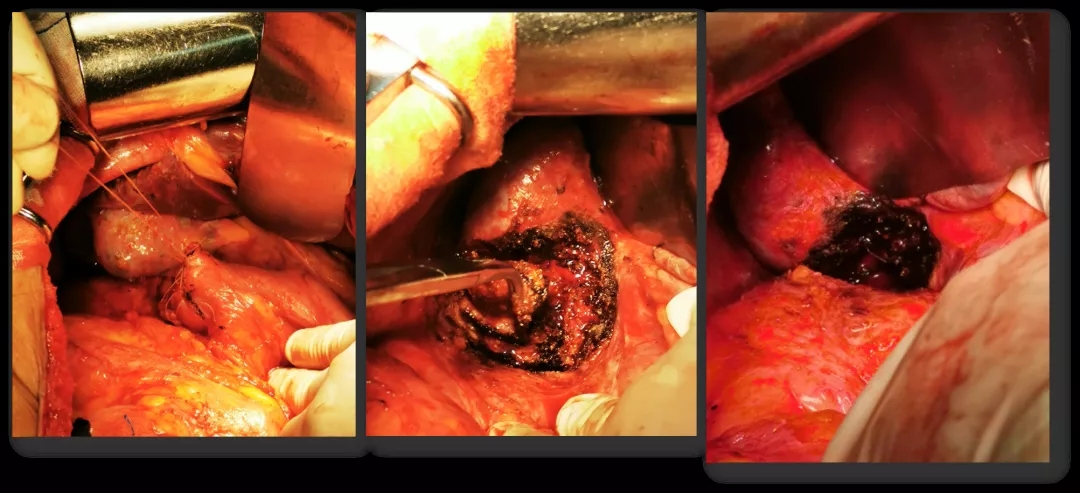

2021.5.18行再次减瘤术(右肝部分切除+十二指肠修补术)。

再次减瘤术

术后病理